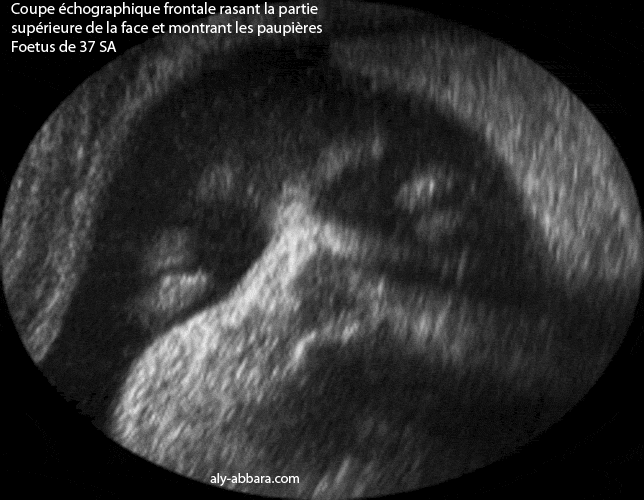

Image en deux dimensions, montrant l'aspect échographique des paupières sur une coupe frontale oblique rasant la partie supérieure de la face.

Fœtus âgé de 37 semaines d'aménorrhée

• Paupière (eyelid) :

• Chacune des membranes mobiles qui recouvrent et protègent la partie antérieure du globe oculaire.